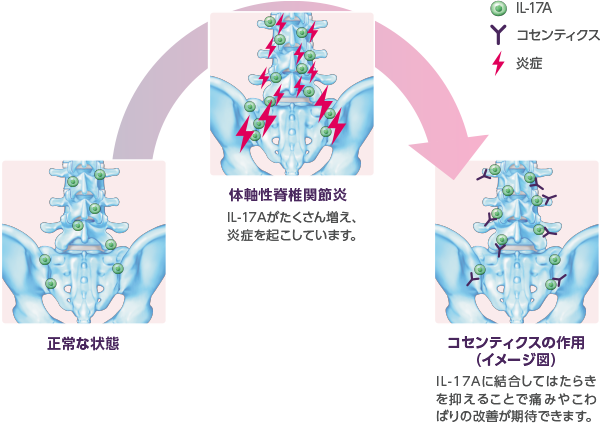

非放射線撮影による軸性脊椎関節炎 (nr-axSpA) は、脊椎および骨盤の仙腸関節 (SI) の慢性炎症状態です。

これは軸性脊椎関節炎 (axSpA) のスペクトルの一部であり、単純 X 線写真 (X 線) で仙腸関節に目に見える損傷がない場合に axSpA を表します。

nr-axSpA の正確な原因は明らかではありませんが、過剰な免疫反応、遺伝学、環境要因がすべて関与している可能性があります。他の関節炎症状と同様に、nr-axSpA は筋骨格系の持続的な炎症を引き起こし、不快感や機能制限を引き起こします。

Nr-axSpA は、脊椎と骨盤に影響を及ぼす慢性炎症状態である axSpA の症状です。理由は十分には理解されていませんが、nr-axSpA およびその他の axSpA の状態は、体の他の領域に合併症を引き起こすことがよくあります。